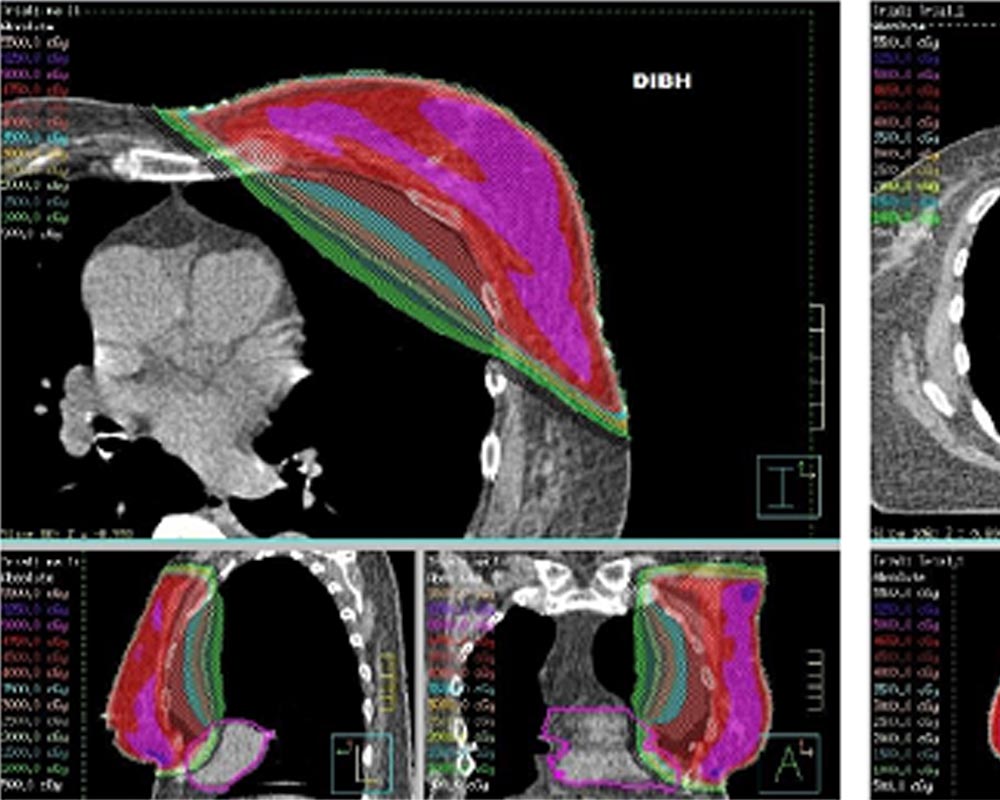

Real time SGRT solution for the whole 4D treatment workflow, from Setup and Positioning to Intra-Fraction Motion Monitoring to Respiratory Gating Treatment.

Breath-hold, deep inspiration and coached/free breathing modes are all supported.

Optional audio-visual coaching helps the patient follow optimal breathing patterns. Patient baseline is calculated as an absolute parameter that can be used during treatment delivery.